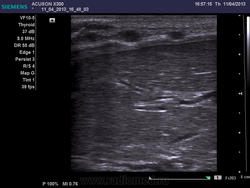

Карциноматоз брюшины - это гипоэхогенные овальные участки?

Да, мелкие гипоэхогенные образования на брюшине, в скан попали два, а на самом деле они множественные.

Да, мелкие гипоэхогенные образования на брюшине, в скан попали два, а на самом деле они множественные.

Спасибо! Вопрос, а гипоэхогенные структуры это не хрящевая часть рёбер в поперечном срезе?

Нет, посмотрите какие маленькие размеры - исследование линейным датчиком.